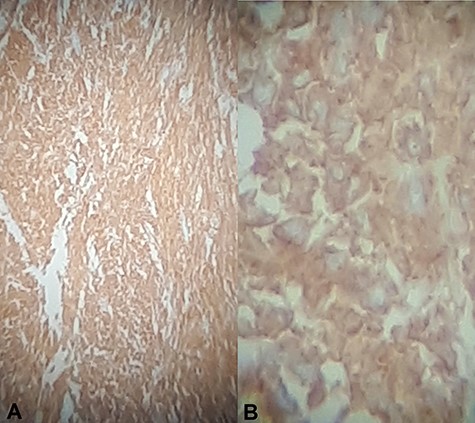

Histology showed a mixed cell type jejunal GIST with a mitotic index of <5/50 HPF—High Power Fields, clear resection margins and an intact tumour capsule (Figs 4 and 5).

Hematoxylin and eosin stain (A) Jejunal mass at ×4 magnification, (B) jejunal mass at ×40 magnification: consist of spindle cells of varying cellularity, hyperchromatic and nuclear pleomorphism with areas of epithelioid cells (mixed type GIST).